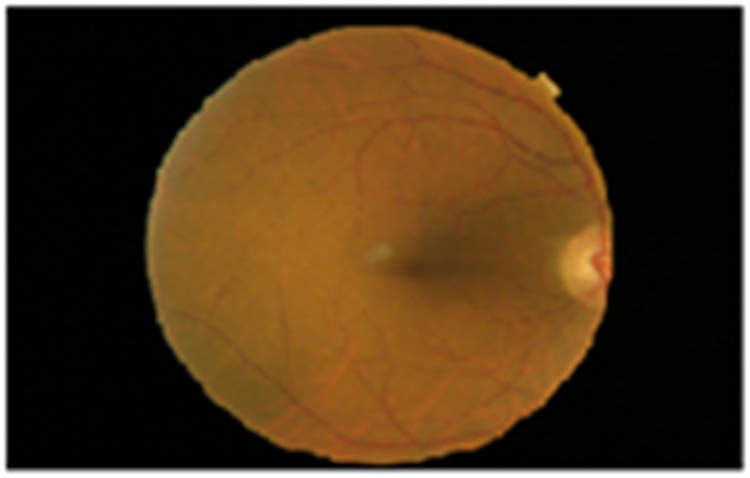

The retinal images were taken individually from all the databases and were subjected to contrast enhancement using CLAHE. Input image is shown in Figure 2. Blood vessel enhanced image is shown in Figure 3.

Input image.